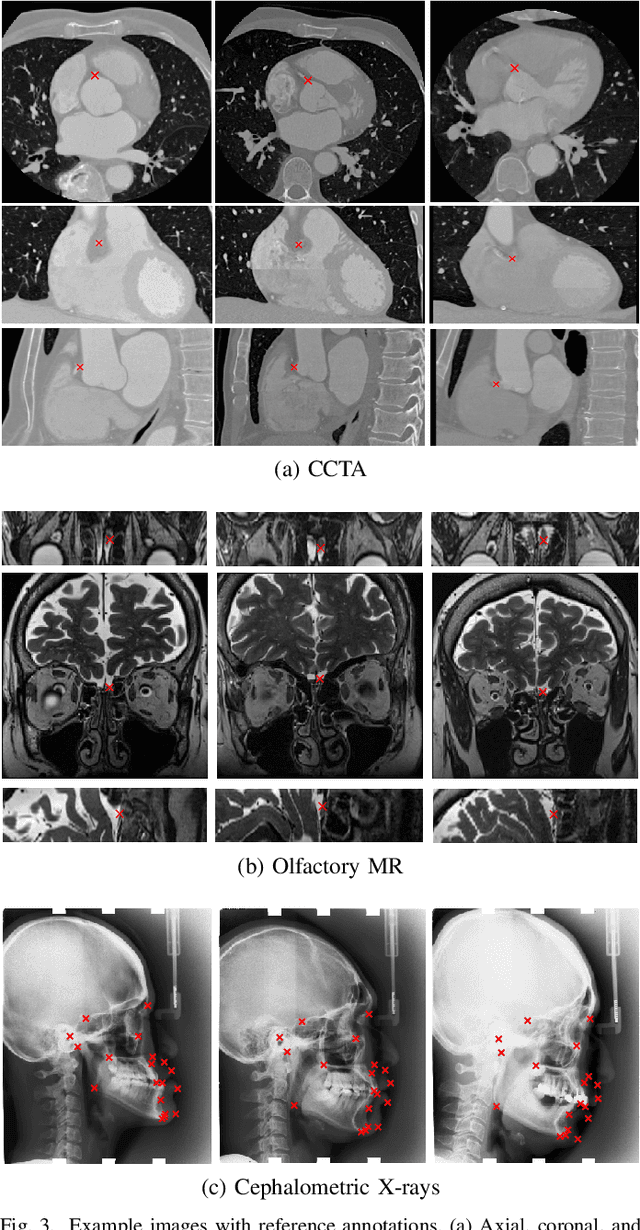

Abstract:In this study, we propose a fast and accurate method to automatically localize anatomical landmarks in medical images. We employ a global-to-local localization approach using fully convolutional neural networks (FCNNs). First, a global FCNN localizes multiple landmarks through the analysis of image patches, performing regression and classification simultaneously. In regression, displacement vectors pointing from the center of image patches towards landmark locations are determined. In classification, presence of landmarks of interest in the patch is established. Global landmark locations are obtained by averaging the predicted displacement vectors, where the contribution of each displacement vector is weighted by the posterior classification probability of the patch that it is pointing from. Subsequently, for each landmark localized with global localization, local analysis is performed. Specialized FCNNs refine the global landmark locations by analyzing local sub-images in a similar manner, i.e. by performing regression and classification simultaneously and combining the results. Evaluation was performed through localization of 8 anatomical landmarks in CCTA scans, 2 landmarks in olfactory MR scans, and 19 landmarks in cephalometric X-rays. We demonstrate that the method performs similarly to a second observer and is able to localize landmarks in a diverse set of medical images, differing in image modality, image dimensionality, and anatomical coverage.